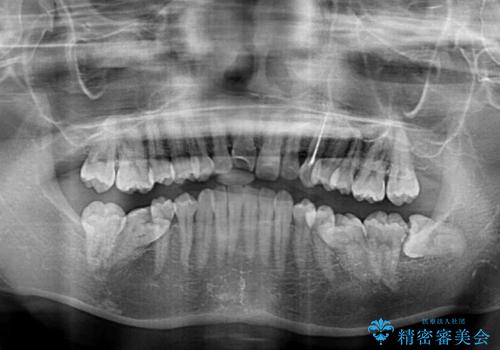

- 前歯のデコボコと奥歯の不正咬合を気にして来院された患者様です。

左右の大臼歯が全て鋏状咬合(シザーズバイト)になっており、治療が難航することが予想されましたが、インビザラインにより治療を行うこととしました。

最難関と思われたシザーズバイトは比較的短期間で解消されました。

しかし、治療中に2度の出産を経験され、治療期間は長くなってしまいましたが、咬みやすく、清掃しやすい歯列を獲得することができました。